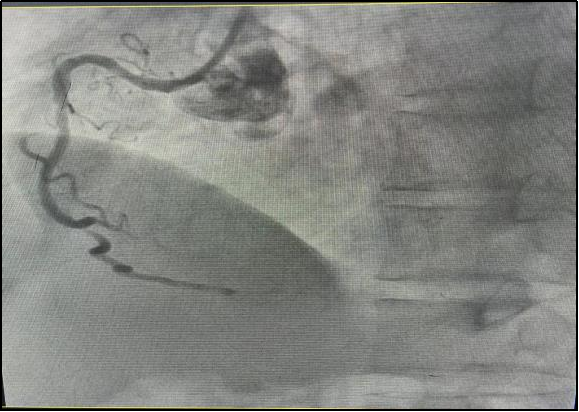

“发热”对于大家来说应该都不陌生吧?但是仅有发热症状的急性心肌梗塞大家听过吗?近日,我院急诊医生在接诊时细心观察,及时发现一名仅有发热症状的急性心肌梗塞患者,并通过介入手术成功挽救其生命。

黄叔基础血压较高,血压基本都在160/90mmHg以上,本次就诊时血压虽然看上去处于正常范围,但血压在短时间内下降超过30%,提示可能存在休克的状态。